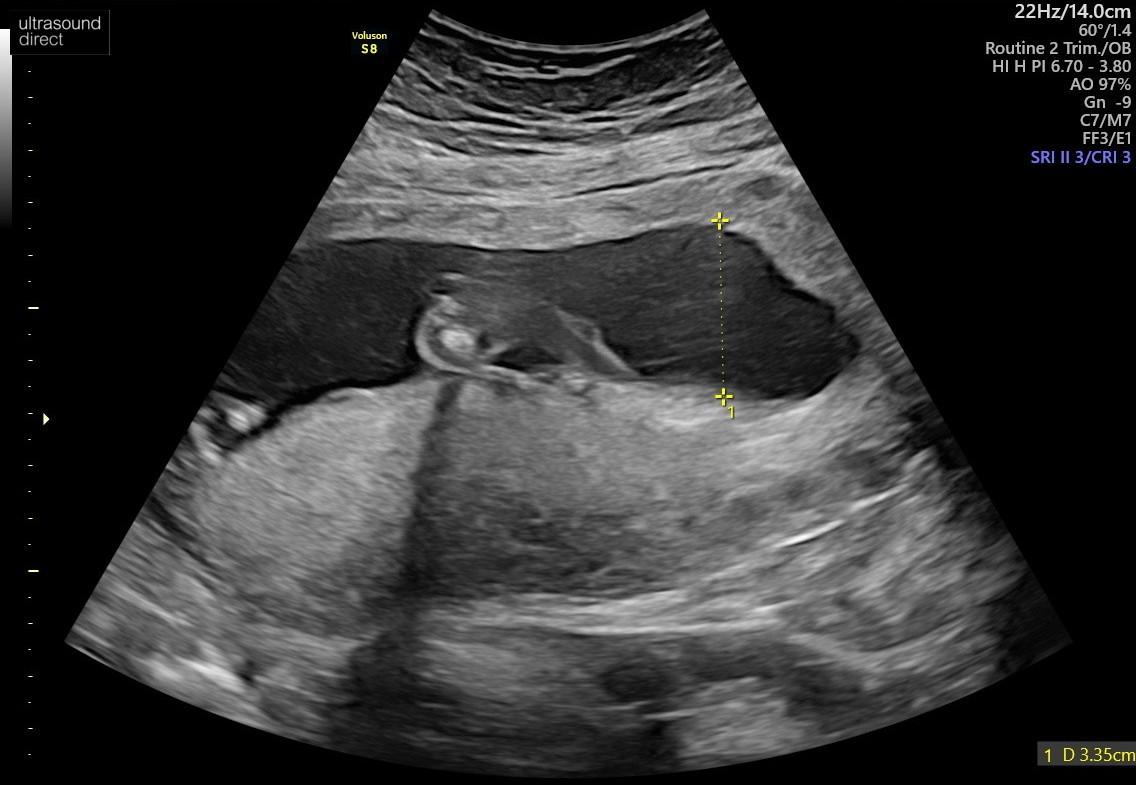

Wg mnie wygląda to na dziecko...Witajcie

Może sprawne oko którejś mamusi podpowie czy po tym rozmazanym USG można stwierdzić płeć maleństwa![]()

Nie da się stwierdzić płci po tych zdjęciach... A lekarz nic nie powiedział?Witajcie

A mi pani doktor powiedziała "dziewczynka" a pan doktor na prenatalnych "chłopiec"Wg mnie wygląda to na dziecko...

Poważnie, jak lekarz nie powiedział płci to losowe osoby z forum powiedzą.

A jak powiedział płeć to możesz mu zaufać lub powtorzyc badanie u innego specjalisty.

Wystarczy zaczekać do kolejnej wizyty i zapytać. A jak się niecierpliwisz to zadzwoń i niech sprawdzą w karcie jaka płeć.Nie chodzi tu o brak zaufania do lekarza tylko o to, że w dniu USG mamusia nie chciała znać płci dziecka.

Ciekawość jednak wzięła górę

I wiem, że lekarzami nie jesteśmy (przynajmniej w większości) więc nie ma co się spinać. Za to są tu mamy z różnym doświadczeniem i na ich opinię liczę![]()